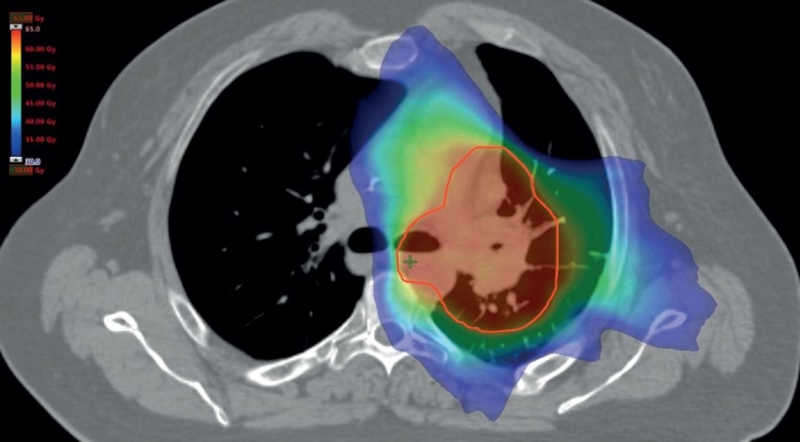

• Xạ trị: Bức xạ giúp hướng chùm tia X năng lượng cao vào khối u và tiêu diệt chúng. Bạn có thể được điều trị xạ trị đơn lẻ hoặc kết hợp với các phương pháp điều trị khác, như phẫu thuật. Phương pháp này được lựa chọn tùy thuộc vào giai đoạn ung thư của bạn, bạn có thể được xạ trị để điều trị u tuyến ức, ung thư tuyến ức hoặc ung thư hạch.